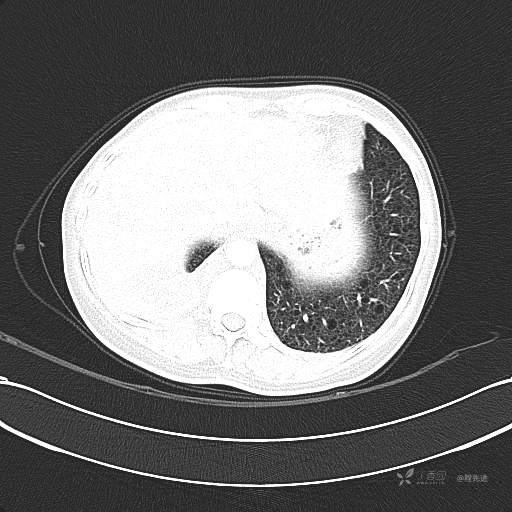

患者性别:女

患者年龄:51岁

简要病史:胸闷半年